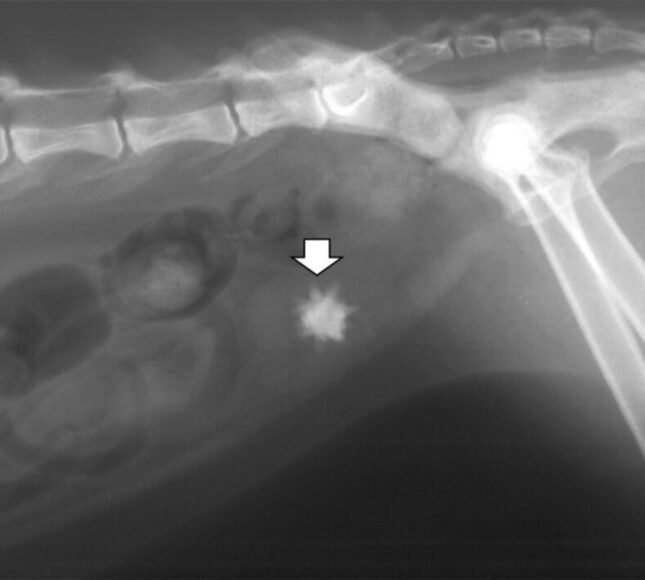

როდესაც მიდიხართ მიღებაზე ასეთ ცხოველთან ერთად, თქვენ უნდა გქონდეთ გათვლილი თქვენი ფინანსები. რატომ? იმიტომ, რომ ასეთ შემთხვევებში პირველ რიგში საჭიროა:

- სისხლის საერთო ანალიზი;

- ბიოქიმია;

- იდეალურ შემთხვევაში, შარდის ანალიზიც;

- ულტრაბგერითი გამოკვლევა (ექოსკოპია).

ეს არის ოთხი რამ, რაც კეთდება ნებისმიერ შემთხვევაში.

თუ ექიმები ხედავენ, რომ შარდის ბუშტი მთლიანად სავსეა და შარდი საერთოდ არ გამოიყოფა, მაშინ ყენდება კათეტერი. ეს ზოგჯერ ნარკოზის ქვეშ კეთდება, ზოგჯერ უბრალოდ ტკივილგამაყუჩებელი ინექციების ქვეშ. ძირითადად, სამი დღით დგება ეს კათეტერი შარდსადენში. ცხოველი დადის პამპერსით, უტარდება სხვადასხვა მკურნალობა, აუცილებლად უკეთდება წვეთოვანი გადასხმები და სამი დღის შემდეგ კათეტერი იხსნება. თუ თქვენს ცხოველს ყველაფერმა გაუარა, კენჭები თუ ქვიშა გამოვიდა, მაშინ მკურნალობა გრძელდება კათეტერის დაყენების გარეშე.